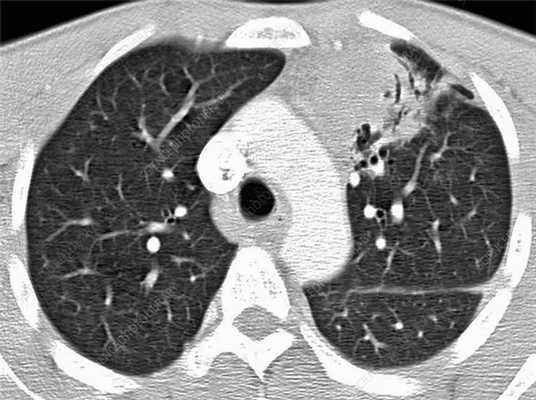

- Рентгенологическая картина. Туберкулез внутригрудных лимфатических узлов часто обнаруживается после проведения рентгенографии легких ребенку, имеющему вираж или гиперергическую реакцию пробы Манту. Инфильтративную форму отличают размытость наружных очертаний, небольшое расширение и смазанность тени корня легкого. Кальцинаты определяются в виде неравномерных округлых или овальных теней. При опухолевидной форме заметны расширение, удлинение и усиление интенсивности тени корней легких, имеющих четко очерченный бугристый контур. В диагностике «малых» форм на стадии инфильтрации пользуются косвенными рентгенологическими признаками. Для уточнения размеров и структуры лимфоузлов применяется МСКТ грудной клетки.

![КТ ОГК. Подтвержденный туберкулез лимфоузлов средостения. Увеличение медиастинальных лимфоузлов (красная стрелка), кальцинаты в л/узлах (зеленая стрелка).]()

КТ ОГК. Подтвержденный туберкулез лимфоузлов средостения. Увеличение медиастинальных лимфоузлов (красная стрелка), кальцинаты в л/узлах (зеленая стрелка).